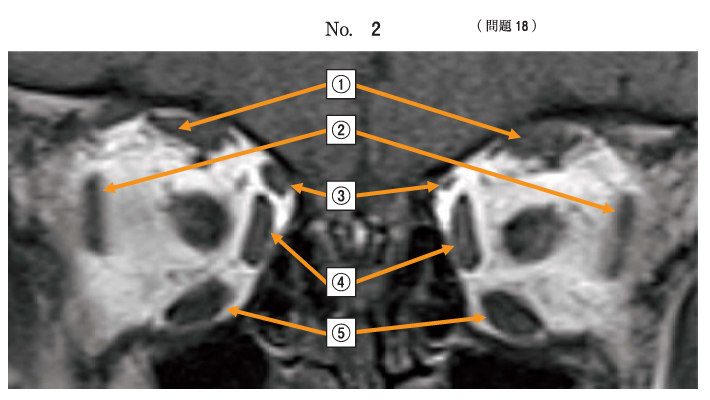

18 眼窩のMRI T1強調冠状断(別冊No. 2)を別に示す。左眼上斜視および外方回旋斜視の原因と考えられるのはどれか。

1.①

2.②

3.③

4.④

5.⑤

正解・・3

上斜筋麻痺が考えられます。上斜筋は③。